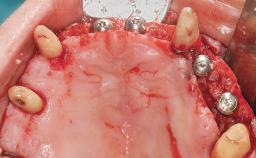

A 63-year-old male patient was referred for a consultation and treatment of partial edentulism in the maxilla. The patient presented with residual anterior teeth and declined a partial removable prosthesis. He reported that the maxillary posterior teeth had been extracted due to mobility and periodontal disease two months before the consultation. The patient’s chief complaint was that his residual maxillary teeth were mobile and that he was unable to chew. The patient’s desire was a stable and comfortable fixed maxillary rehabilitation. The patient was a light smoker (fewer than 10 cigarettes/ day), and his medical history was without significant findings. He was not on any regular medication at the time of consultation. The extraoral examination revealed a normal physiognomy with a correct distribution of the facial thirds. The patient presented a low lip line, and the transition line between teeth and soft tissues was not exposed during a forced smile.

Bone Augmentation Horizontal|Simultaneous

Bone Volume Horizontally and vertically sufficient